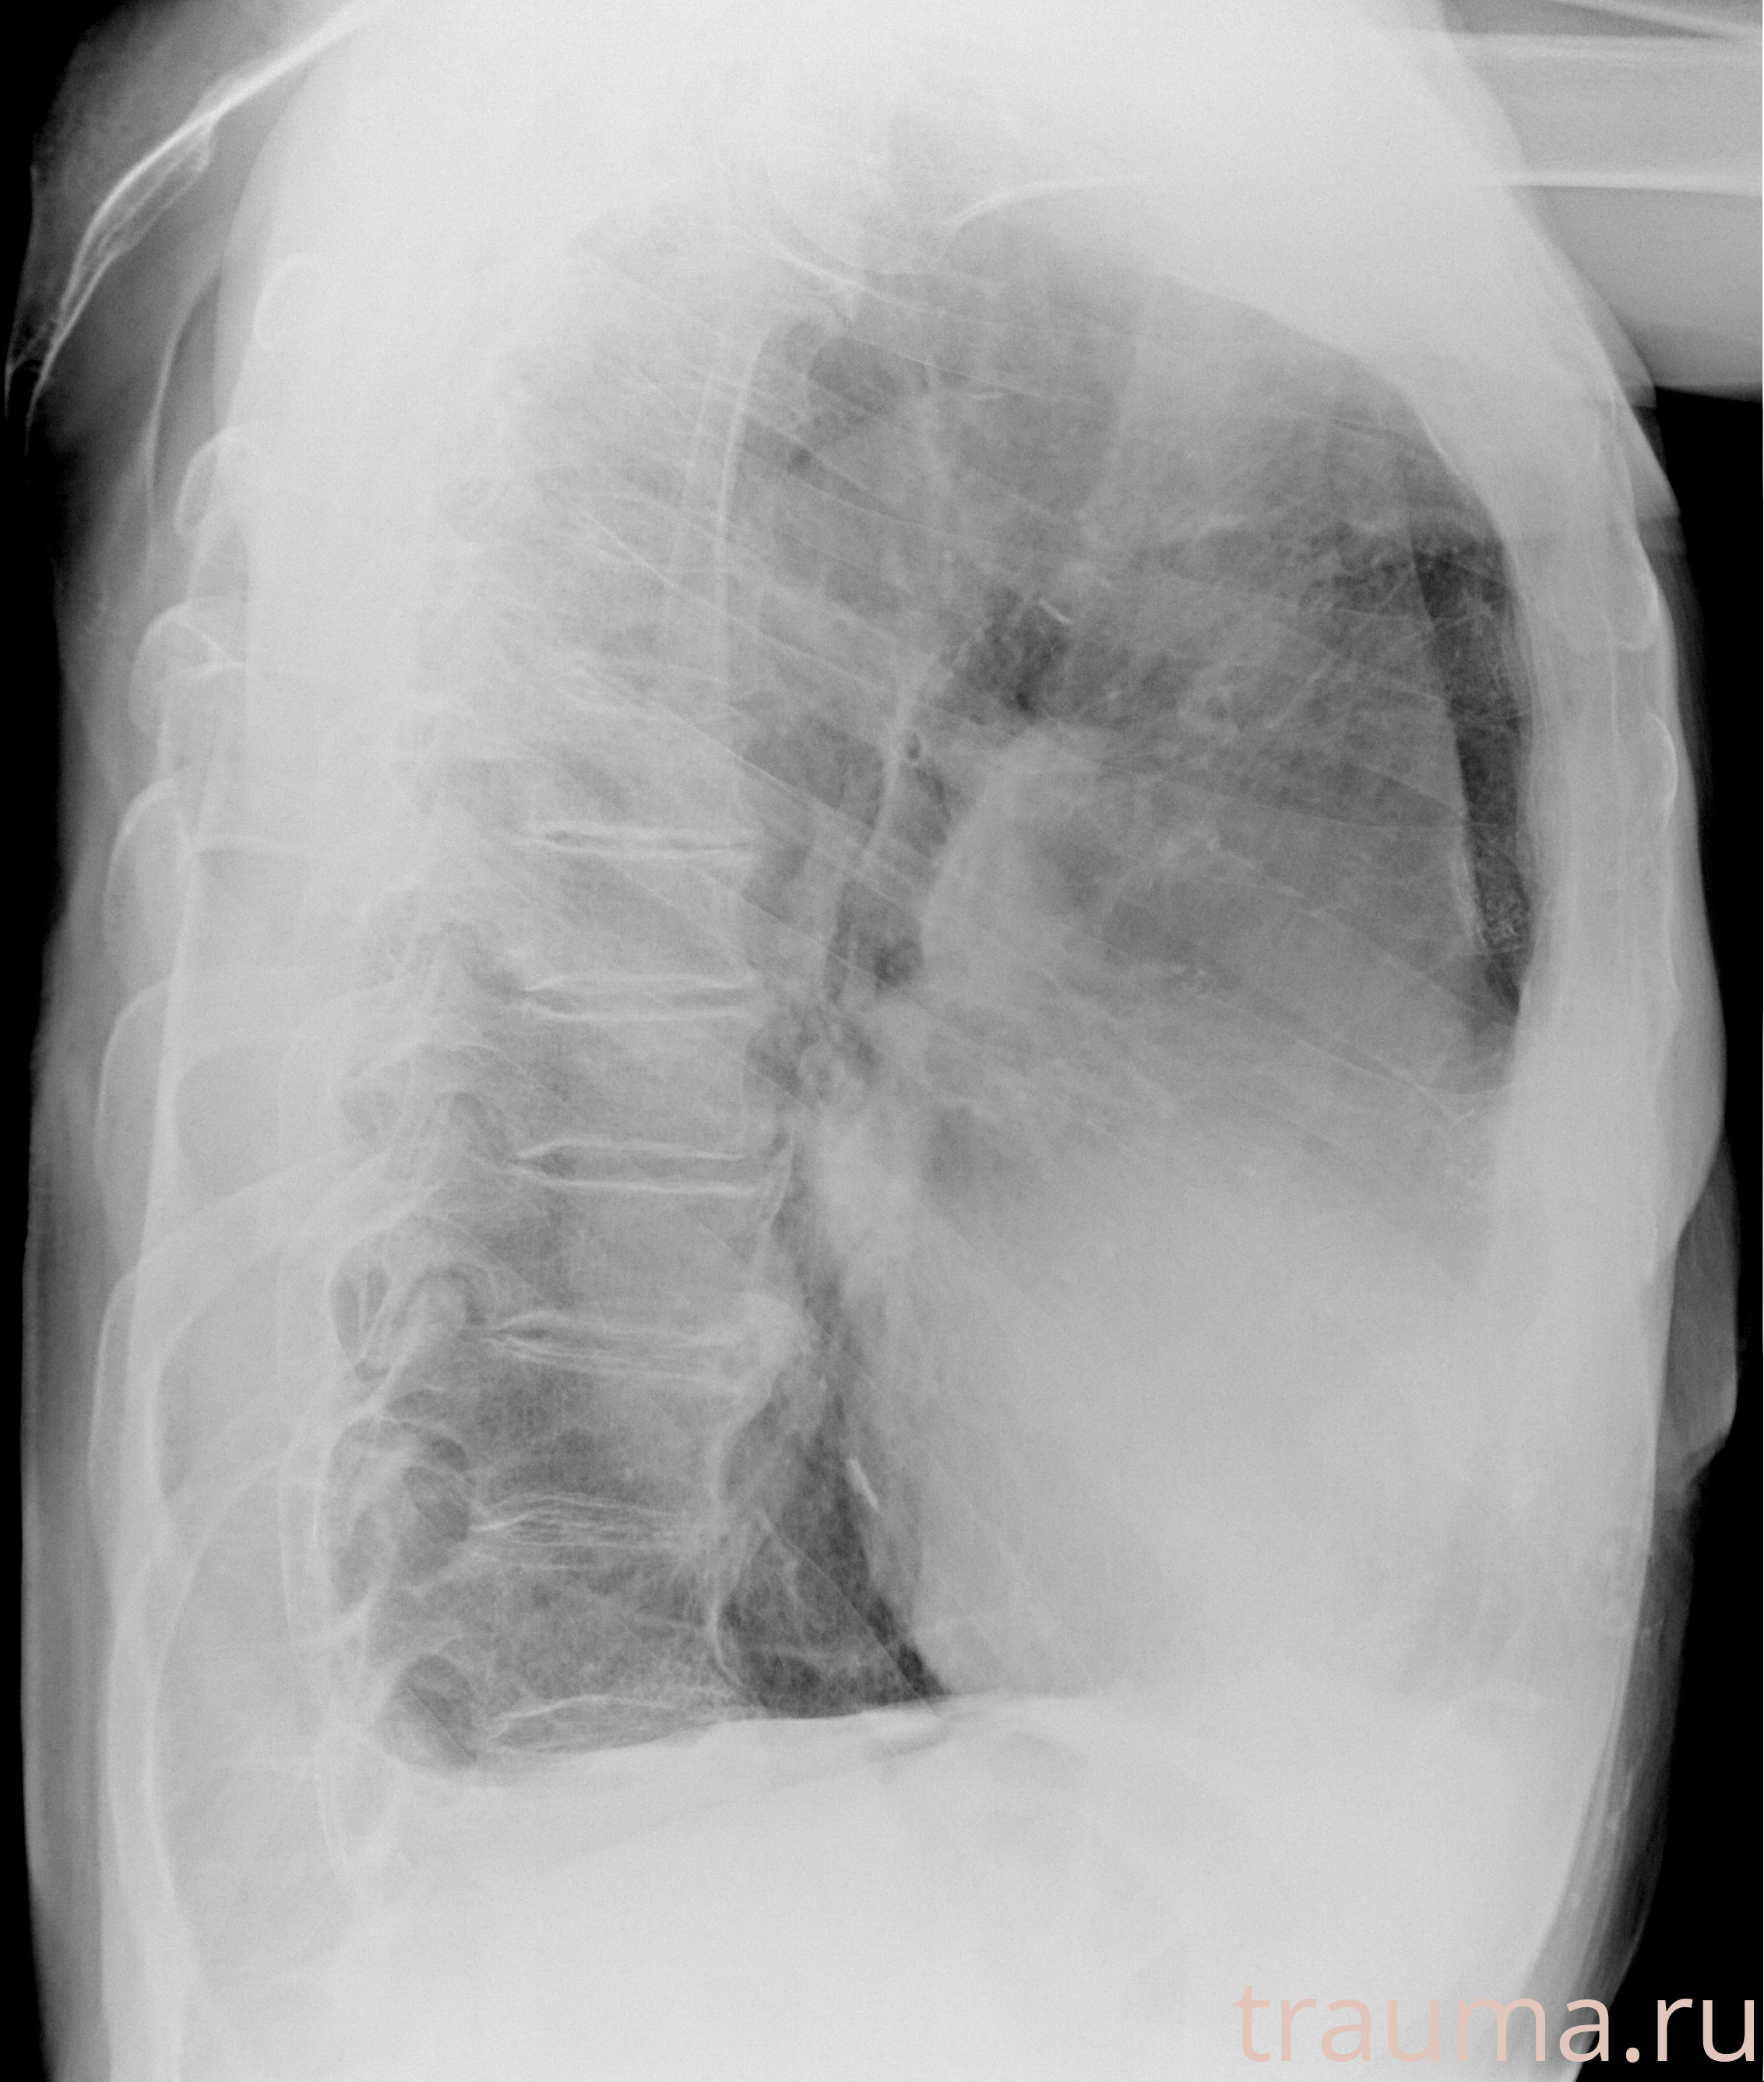

Рентгенограммы

Рентген на дому: по вашему адресу приезжает врач-рентгенолог, травматолог-ортопед с мобильным рентгеновским аппаратом, проводит диагностику травмы или заболевания, делает необходимые рентгенограммы, дает рекомендации по дальнейшему лечению. Получить качественные снимки в домашних условиях возможно благодаря уникальной методике, разработанной МосРентген Центром для института  Склифосовского